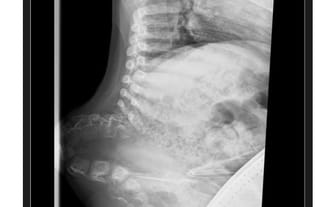

Aktualnie kręgosłup Jacka wygląda właśnie tak, jak prezentuje zdjęcie. Sytuacja pogarsza się z dnia na dzień.

Postępujące skrzywienie kręgosłupa powoduje, że tułów niebezpiecznie się skraca, co powoduje, że rosnące organy niebezpiecznie naciskają na płuca. Już na tym etapie, lekarze potwierdzili, że płuca mają o połowę mniej miejsca niż to przewidziane u zdrowego dziecka w tym wieku. Taki ucisk to prosta droga do niewydolności oddechowej.

Nie wyobrażam sobie tej kwoty, ale operacje muszą odbywać się regularnie, by skrzywienie się nie pogłębiało, a organizm był bezpieczny. By Jacek mógł zdrowo rosnąć, nie czując przy tym rosnącego bólu, dyskomfortu podczas jedzenia, zmęczenia podczas siedzenia. Nie wyobrażam sobie tego, by zaistniała sytuacja, trwałe wpłynęła na możliwości jego rehabilitacji i samodzielnego poruszania.... Niewydolność oddechowa może spowodować, że nawet na wózku inwalidzkim nie będzie mógł być samodzielny. W tym momencie jego ciało jest dla niego największym zagrożeniem...